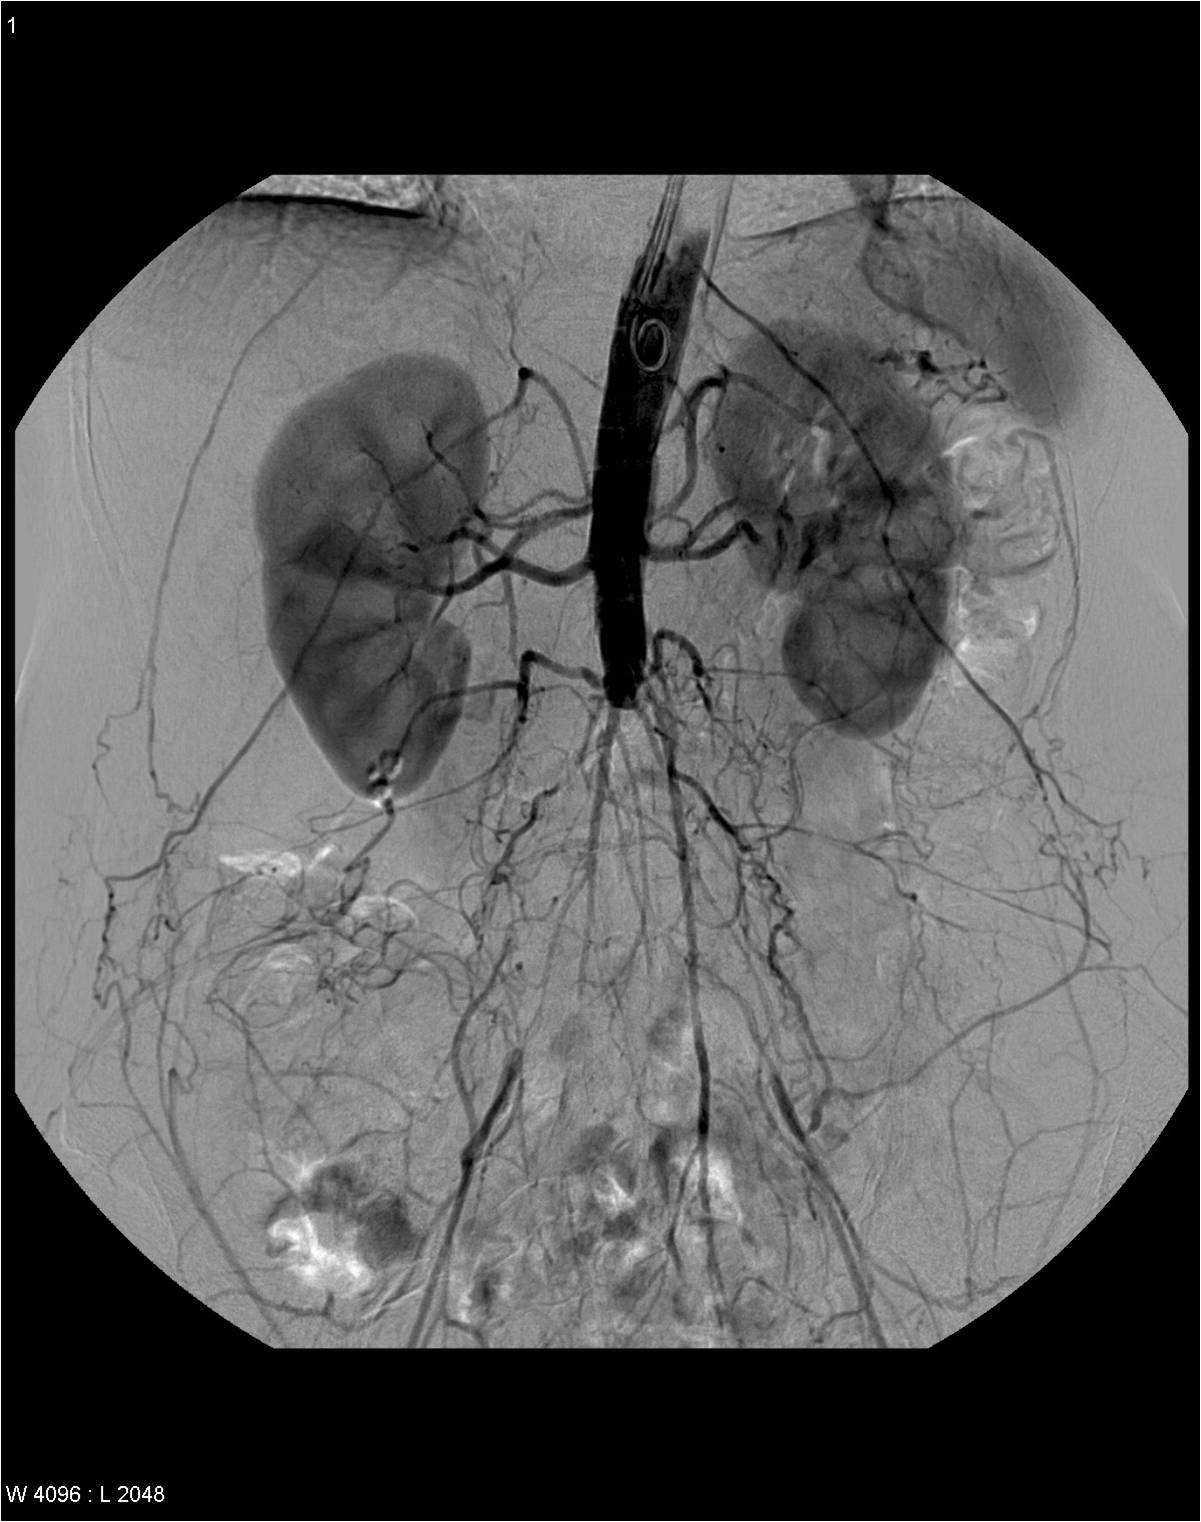

Image

Contrast enhanced MR angiography

Control CT angiography after stent implantation to correct a bilateral arterial stenosis

Fig. 18., 19.: Renal artery stenosis